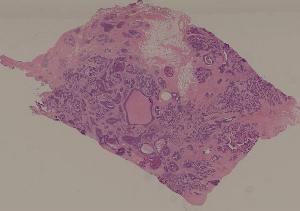

80.乳腺浸润性导管癌